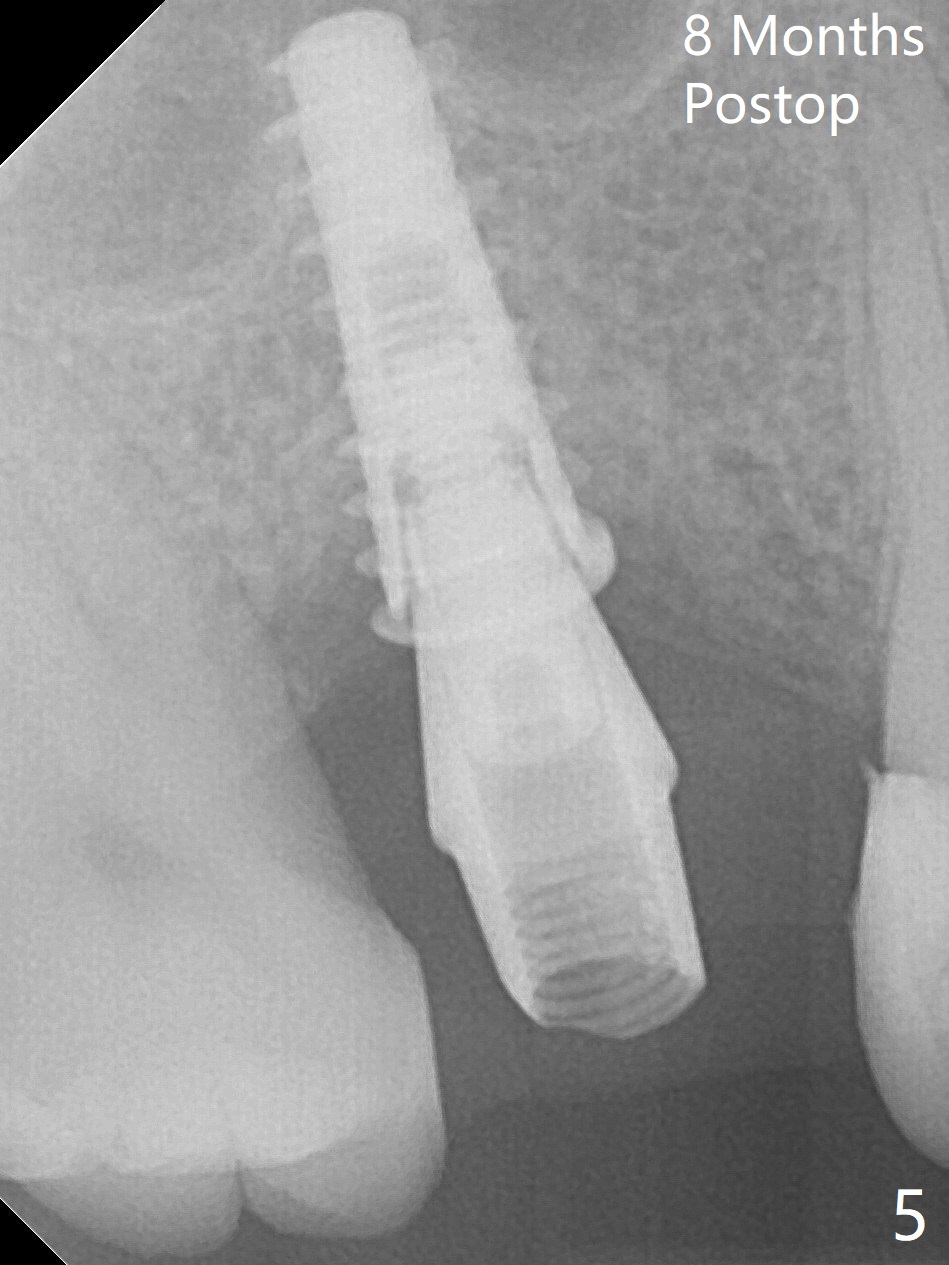

There are 2 sockets at #3 when the residual roots are extracted; osteotomy is established in the palatal one for 11 mm (gingival level; Fig.1), ~ 2 mm from the sinus floor (red dashed line). Following the last drill (3.8 mm) for 11 mm, a 4.5x11 mm dummy implant is placed 2 mm subgingival (Fig.2). In fact the sinus lift (red dashed line) is done by implant insertion, since the bone plug after Magic Drill is present in the apical portion of the osteotomy when the last drill is finished prior to implant placement.. After the dummy implant is removed, the definitive one (the same size) is placed with >50 Ncm, followed by placement of a 4.5x4(3) mm abutment and VeraGraft mixed with autogenous one (Fig.3 *). The most coronal portion of the socket is sealed with collagen plug. The latter is fixed in place by an immediate provisional. The mesial surface of the tooth #2 is reduced (Fig.4 <) prior to provisional fabrication. The implant is placed distal, which could be corrected by pushing the 2nd molar distal orthodontically. There is mild crestal bone loss nearly 8 months postop (Fig.5). An angled abutment (5x15 degrees, 3 mm cuff) is used before impression. CT is taken immediately post cementation (Fig.6 (8.5 months postop)). CT taken 8 months post cementation shows that the 4.5x11 mm implant barely passes the sinus floor (Fig.7). Return to Upper Molar Immediate Implant, Prevent Molar Periimplantitis (Protocols, Table), IBS, 30 19 Xin Wei, DDS, PhD, MS 1st edition 09/13/2017, last revision 01/31/2019